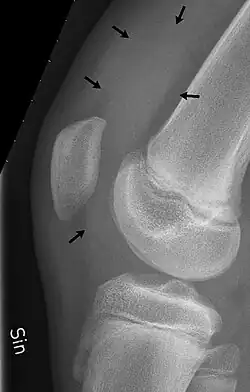

| Traumatic effusion of the right knee, with swelling lateral to the kneecap marked by an arrow | |

An X-ray may be recommended by your provider as a way to obtain a 2-dimensional image to visualize the joint in question. In the presence of trauma an X-ray can be especially useful to verify that there is no break, dislocation, or deformity. In an atraumatic knee, an X-Ray can be used to identify or rule out other causes of a knee infusion including some inflammatory or age-related causes.